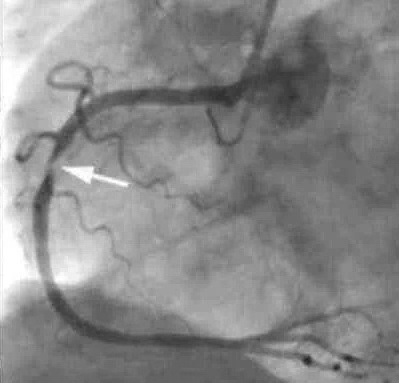

做冠脉造影,果不出所料,心脏三根血管均有狭窄,右冠脉重度狭窄,植入一枚支架。